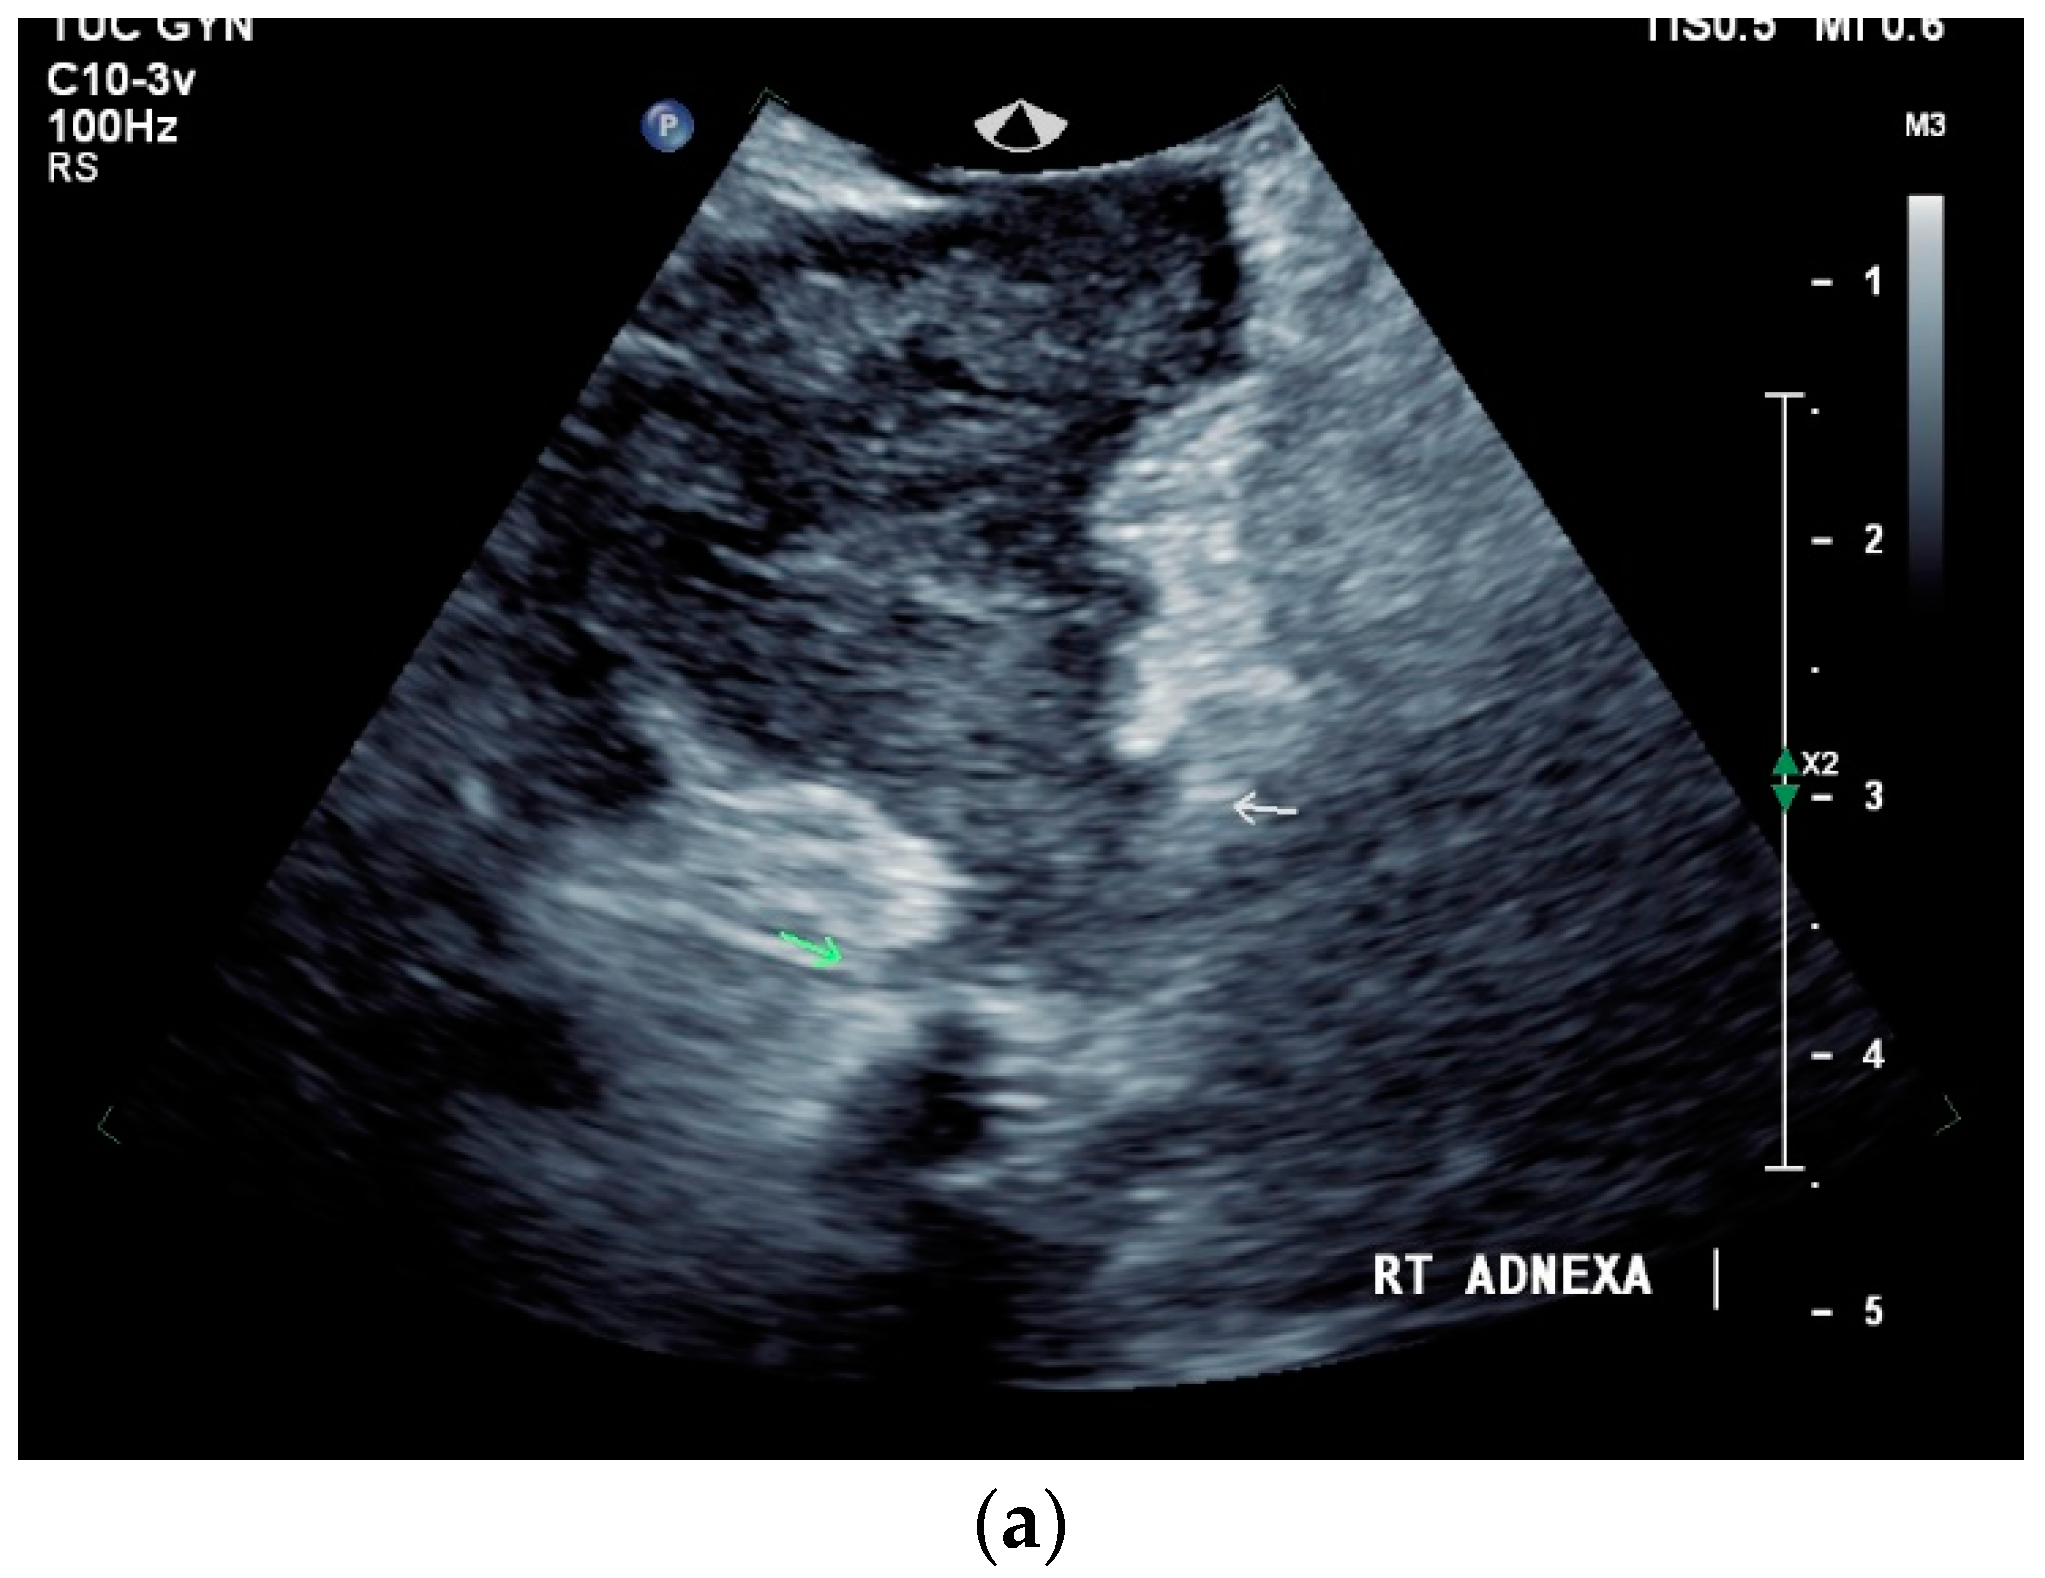

13.2. Adnexa, Fallopian Tubes, Uterus

Signs of tuberculosis in abdominal or vaginal ultrasounds in the female genital area are ovarian cyst, tubo-ovarian mass, hydrosalpinx, pyosalpinx, adhesion, adnexal fixation, thin endometrium, endometrial fluid, endometrial calcification, endometrial synechiae (Asherman’s syndrome), cornual synechiae, disturbed endometrial vascularity, ascites in the small pelvis, and peritoneal or omental thickening [122]. In a study with 175 infertile patients, ovarian cysts (23.4%) and tubo-ovarian masses (15.4%) were the most common manifestations [122] [Figure 8a–e].

Figure 8.

Tuberculosis of the uterus and adnexae. Female patients with tuberculosis in India. Pelvis with tubo-ovarian masses: Hypoechoic lesion in right adnexa (arrows) (a) and hypoechoic lesion in left adnexa and a small amount of free fluid (arrows) (b). Free fluid in the Douglas space (arrows) (c). Thickened right fallopian tube (RT FT) (arrows) (d); thickened left fallopian tube (LT FT) (arrows) (e).